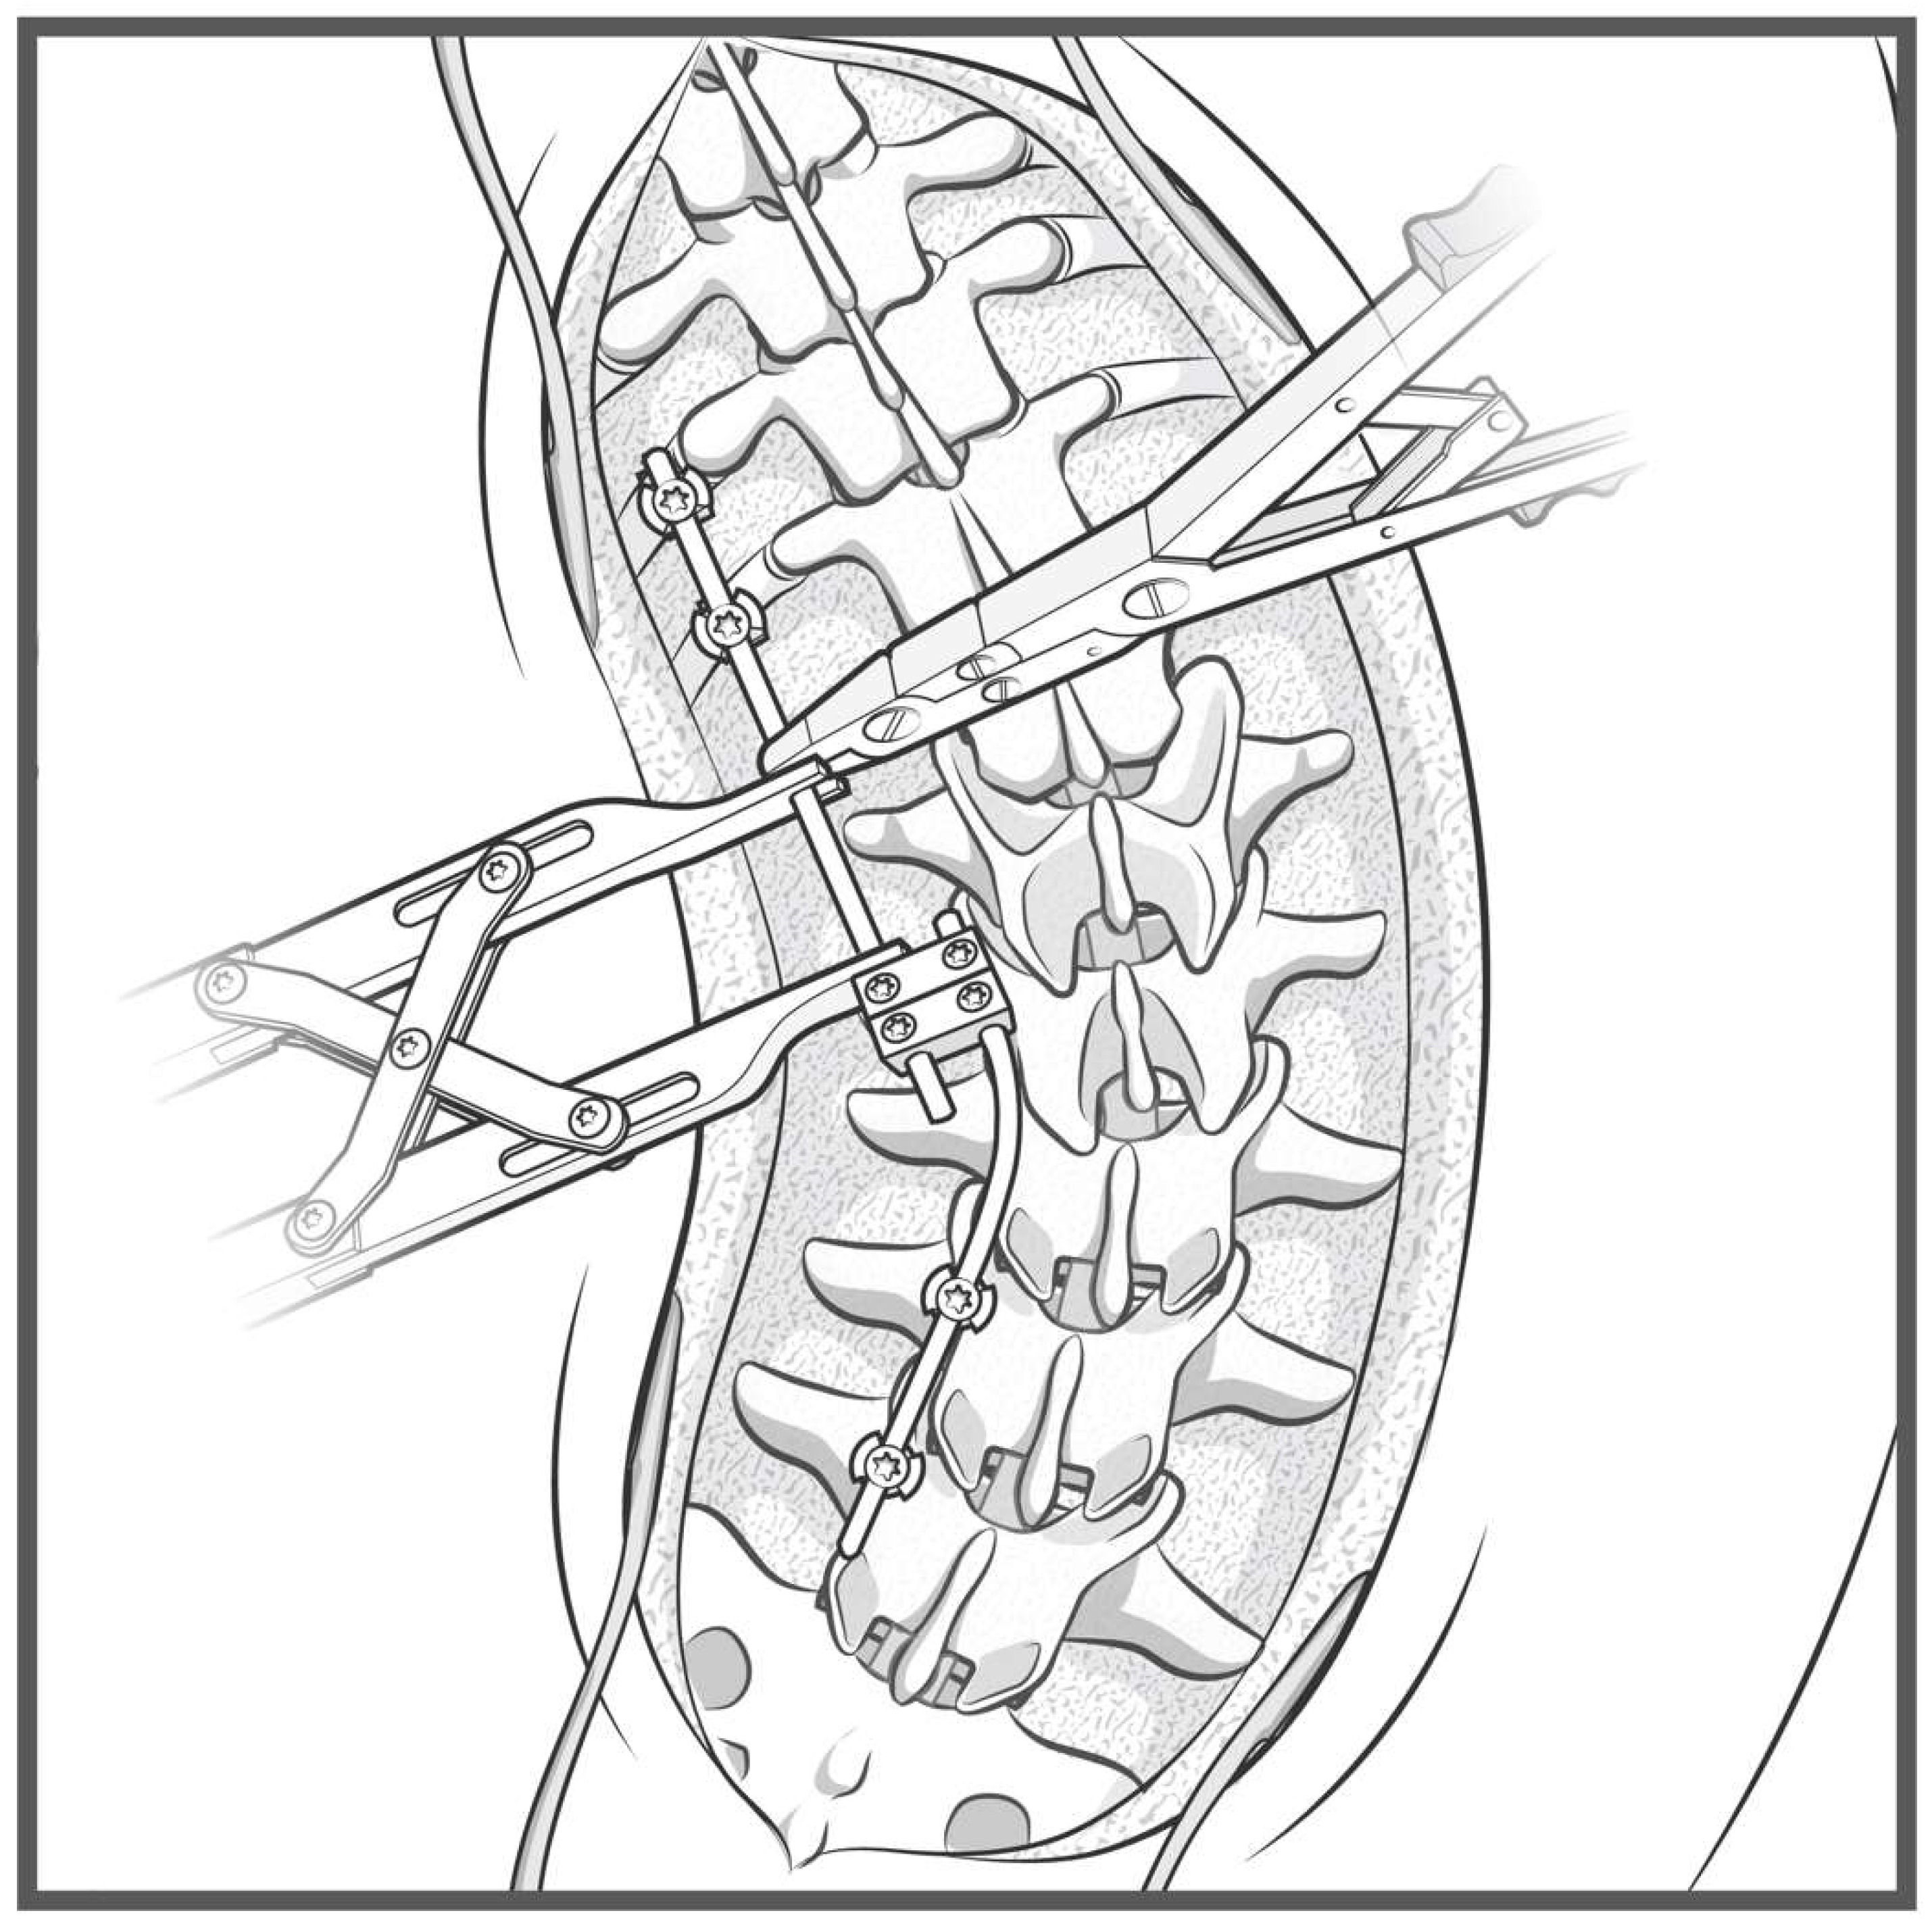

A detailed surgical technique guide by Buchowski et al. in 2007 describes temporary internal distraction in a broader context and highlights important considerations, such as preoperative surgical planning, patient positioning, and placement of proximal and distal anchor points [4]. However, this report aims to focus on the placement and configuration of spinal rods for internal distraction or compression utilizing the construct-to-construct technique. To set up the construct-to-construct configuration, one rod is attached to the proximal anchor points and a second rod to the distal anchor points. There should be at least two (or more) anchor points at the proximal and distal ends to set up this technique. This helps prevent plowing of pedicle screws by distributing the distractive and compressive forces across several motion segments along the spine. These rods are joined by one or two lateral domino connectors to complete the construct-to-construct setup. The more overlap of the rods, the more “runway” there is to apply distraction (Figure 1). Conversely, the less overlap that exists between these two rods, the more “runway” there will be to apply compression (Figure 2). If internal distraction is desired, this construct-to-construct configuration will need to be set up on the concavity of the scoliosis curve. Alternatively, the construct-to-construct configuration will need to be set up on the convexity of the scoliosis curve if internal compression is needed. Distraction or compression is then applied to these rods in a serial, “click-by-click” fashion after loosening the ipsilateral set caps on the domino connectors. Rod grippers may be used to distract or compress against instead of utilizing pedicle screw tulips in order to reduce loosening of the anchor points. After the desired amount of deformity correction is achieved, the set caps on the domino connectors are tightened to hold the correction.

Figure 2.

Sawbone model utilizing a construct-to-construct internal compression technique showing reduced overlap of the rods across the lateral domino connectors, the more “runway” there will be to apply compression.

3.4. Pedicle Subtraction Osteotomy

Pedicle subtraction osteotomies (PSOs) represent Schwab 3 and 4 osteotomies and are powerful techniques for correcting both sagittal and coronal fixed, spinal deformities [7]. The PSO is the first three-column osteotomy described in this technique paper. The construct-to-construct internal compression technique represents one method of closing this osteotomy. We recommend having several anchor points above and below the PSO level (three levels of fixation are preferred if possible). In the case of lumbar PSOs, a contoured rod is fixed to the distal anchor points and cantilevered over the osteotomy to connect into one or two domino connector(s) to form the construct-to-construct configuration [8]. A rod gripper attaches to this distal contoured rod, and a compressor is placed between the domino connector(s) and the rod gripper (Figure 7). Gradual compression is applied in a controlled, “click-by-click” manner before the set caps are tightened to hold the correction. This process is repeated on the contralateral side to finish closing down the osteotomy.